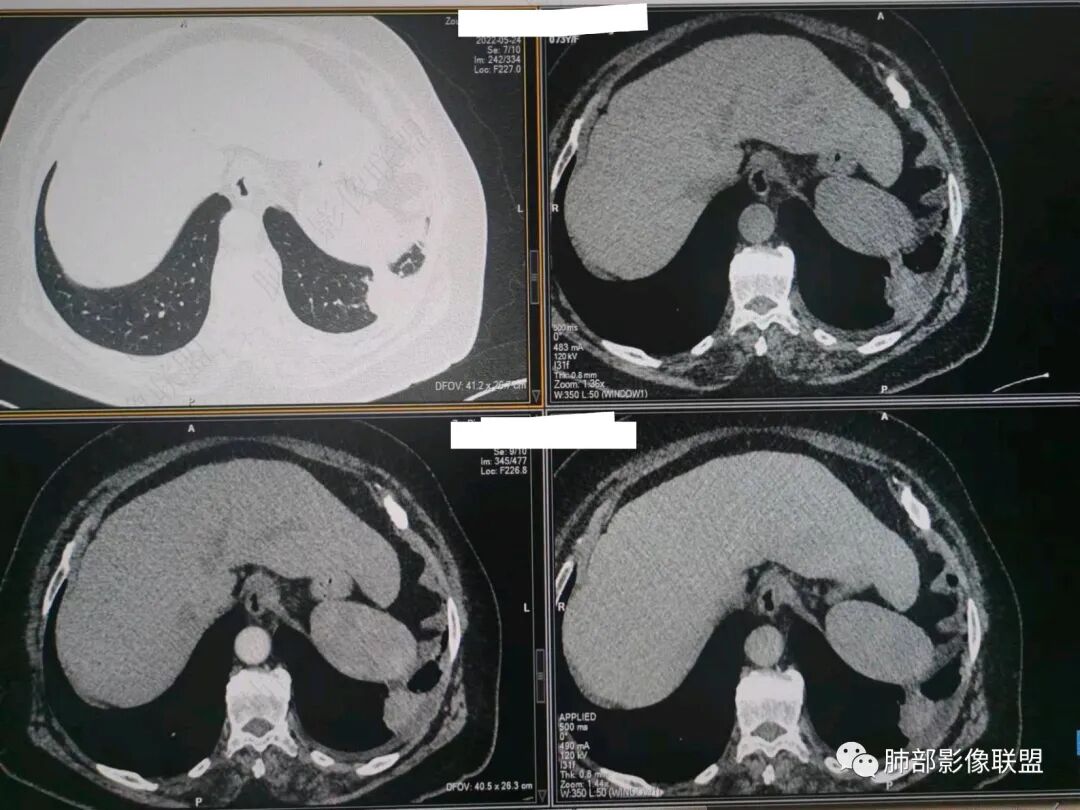

秦化君:左肺下叶外基底段胸膜下软组织密度结节性,边缘毛糙与血管相连,密度不均,增强后病灶内边界不清低密度区,胸膜栽桩,少量胸腔积液。考虑恶性病变,腺癌可能。真菌待排。

谢加平:老年女性,慢性咳嗽,咳白痰史,左肺下叶后基底段胸膜下肿块,类圆形,边界清膨隆,密度不均匀,低强化及小灶性坏死,坏死轮廊不清,胸膜下栽赃明显,左侧胸腔少量积液,向胸壁肌侵犯,另肿块近心侧见支指套征,粘液低密度,支持恶性,粘液腺Ca,经皮肺穿刺活检明确诊断。

361度:老年女性,发热,胸部CT示左下肺胸膜下结节影,血管集束,毛棘,密度不均,胸膜栽赃,少量胸腔积液,不均匀强化,坏死边界不清,肿标轻微升高,考虑恶性,鳞癌合并感染。

宇宙:左肺下叶胸膜下球形肿块,边界尚清,局部平直,局部膨隆,内侧缘长索条,胸膜栽赃,轻度不均匀强化,其内坏死边界欠清,左侧胸水,考虑腺癌,鉴别放线菌。

袁媛:左肺下叶胸膜下球形肿块,宽基底连于胸膜下,胸膜栽赃,边缘膨隆,有血管供应,增强有强化,考虑腺癌。

songml:老年女性,反复咳嗽咳痰胸闷4年,加重伴发热一周。左肺下叶后基底段胸膜下肿块影,密度较均匀,边缘较清,侵及胸膜下脂肪间隙。考虑恶性病变,腺癌可能,鉴别真菌感染。

人生海海:左肺下叶不规则形软组织密度影,膨隆生长,边缘清楚,分叶,棘突征,支气管截断,血管纠集,病灶轻度强化、内多发坏死,左侧少量胸腔积液,考虑粘液腺癌,鉴别肺脓肿。

位移:老年女性,左肺下叶肺胸膜下团块影,边界清、毛糙,膨隆,内密度不均,不均匀强化,内见坏死,胸膜栽赃,胸腔少量积液,首先考虑恶性肿瘤,低分化腺癌,鉴别小细胞癌,炎性假瘤。

赖晓宇:膨隆,浅分叶,支气管截断,内部坏死边界不清,胸膜受累,胸腔积液,考虑恶性。

放射线:左肺下叶后基底段胸膜下肿块,边缘膨隆,密度不均匀,内见低密度坏死,胸膜栽赃,左侧胸腔少量积液,考虑恶性,腺癌?鉴别放线菌,OP伴脓肿。

仲夏:老年女性,咳嗽咳痰近4年,左肺下叶胸膜下类圆形肿块,内侧绳索征,内部密度不均匀,可见坏死,周围小空泡,小叶间隔增厚,胸膜下积液,轻度强化,NSE、细胞角蛋白酶19片段高,考虑恶性肿瘤,腺癌?

南边:今天的病例肺内部分基本都是炎性特点,问题就在于胸膜。

今天的病例有些伪影。

看起来就觉得放射状伪影。

我就不知道这些是胸水,伪影导致密度增高?还是胸膜增厚?

我只是邓较瘦:今天平扫的像栽赃, 增强感觉是增厚的胸膜。